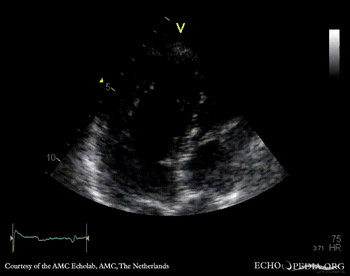

Case 112